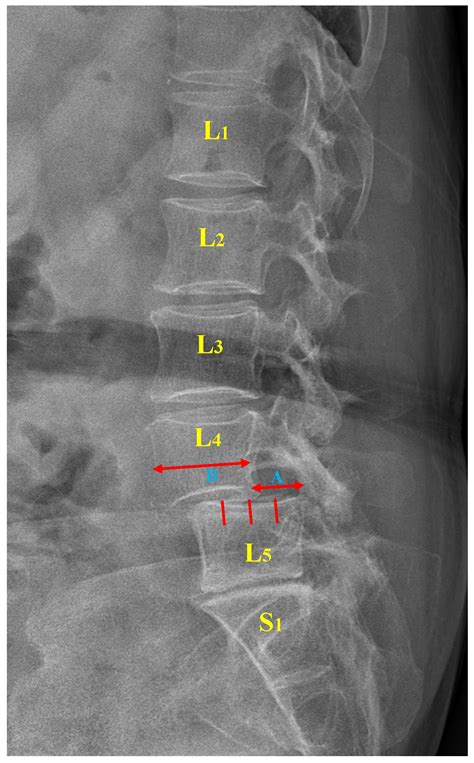

Sex X Ray technology involves the use of X-rays to produce images of the internal structures of the reproductive and sexual organs. This type of imaging is particularly useful for diagnosing conditions that affect the reproductive system, such as tumors, infections, and anatomical abnormalities. The technology works by passing X-rays through the body, which are then captured on a detector to create detailed images.

- Pelvic X-Ray: A general X-ray of the pelvic region that can help identify fractures, tumors, or other abnormalities in the bones and soft tissues.

Interpreting Sex X Ray results requires the expertise of a radiologist. The images are carefully analyzed to identify any abnormalities or conditions. Here are some common findings:

| Finding | Possible Condition |

|---|---|

| Blockages in Fallopian Tubes | Infertility, Pelvic Inflammatory Disease (PID) |

| Tumors or Masses | Cancer, Benign Tumors |

| Anatomical Abnormalities | Uterine Fibroids, Ovarian Cysts |

| Infections | Pelvic Inflammatory Disease (PID), Sexually Transmitted Infections (STIs) |

It is important to discuss the results with your healthcare provider to understand the implications and next steps for treatment.